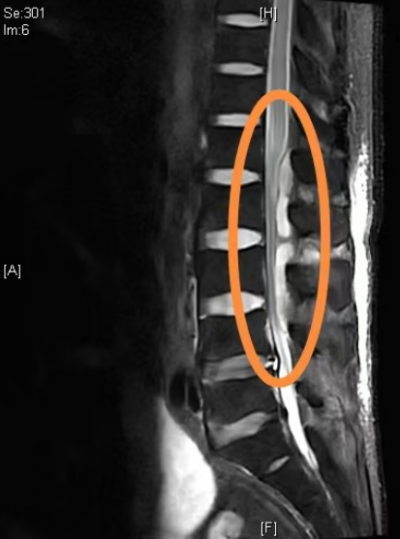

椎管内大量脓肿压迫脊髓

“这位患者原本有二型糖尿病,血糖控制不理想,抵抗力差,属于易感染人群,加上在家自行拔火罐,缺乏专业指导,导致腰部皮肤破损,给金黄色葡萄球菌侵入提供了可乘之机。”曾浩介绍,细菌入血后,感染扩散很快,引发了腰大肌脓肿、化脓性脊柱炎,脓肿压迫脊髓,造成不完全截瘫。